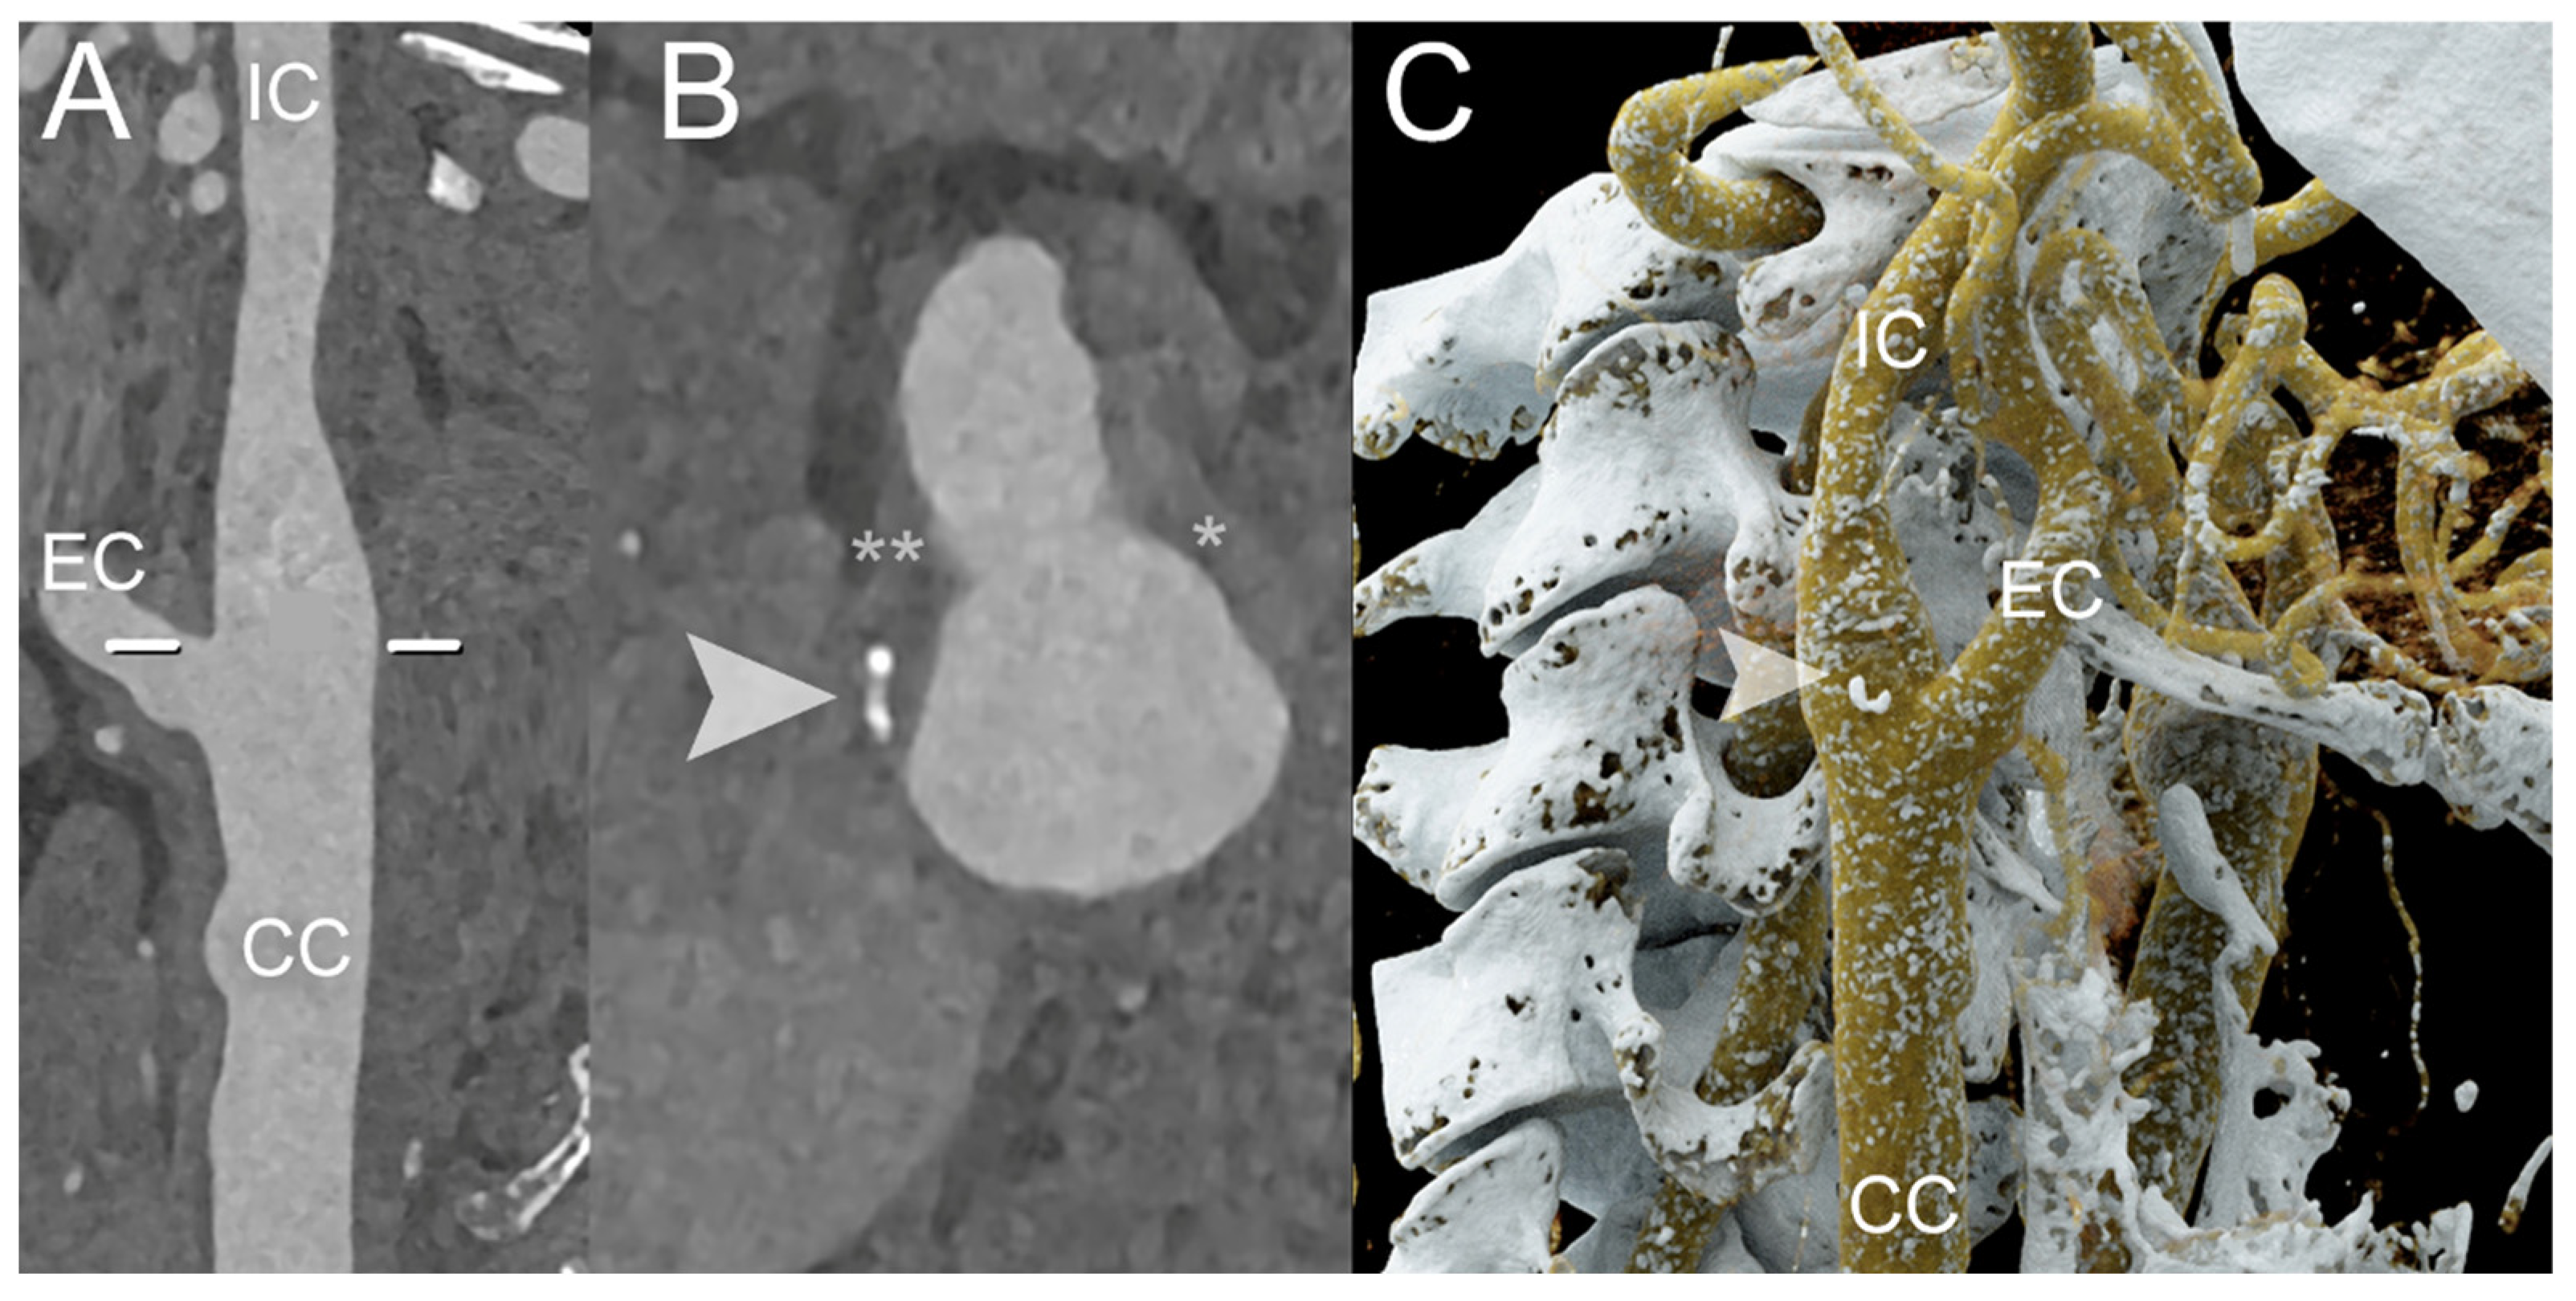

4. Clinical Application of PCCT in Carotid Plaque

- Dahal, S.; Raja, A.Y.; Searle, E.; Colgan, F.E.; Crighton, J.S.; Roake, J.; Saba, L.; Gieseg, S.; Butler, A.P.H. Components of carotid atherosclerotic plaque in spectral photon-counting CT with histopathologic comparison. Eur. Radiol. 2023, 33, 1612–1619. [Google Scholar] [CrossRef]

- Shami, A.; Sun, J.; Gialeli, C.; Markstad, H.; Edsfeldt, A.; Aurumskjöld, M.-L.; Gonçalves, I. Atherosclerotic plaque features relevant to rupture-risk detected by clinical photon-counting CT ex vivo: A proof-of-concept study. Eur. Radiol. Exp. 2024, 8, 14. [Google Scholar] [CrossRef] [PubMed]

- Healy, J.; Searle, E.; Panta, R.K.; Chernoglazov, A.; Roake, J.; Butler, P.; Butler, A.; Gieseg, S.P.; Adebileje, S.A.; Alexander, S.D.; et al. Ex-vivo atherosclerotic plaque characterization using spectral photon-counting CT: Comparing material quantification to histology. Atherosclerosis 2023, 378, 117160. [Google Scholar] [CrossRef]

- Zainon, R.; Ronaldson, J.P.; Janmale, T.; Scott, N.J.; Buckenham, T.M.; Butler, A.P.H.; Butler, P.H.; Doesburg, R.M.; Gieseg, S.P.; Roake, J.A.; et al. Spectral CT of carotid atherosclerotic plaque: Comparison with histology. Eur. Radiol. 2012, 22, 2581–2588. [Google Scholar] [CrossRef] [PubMed]

- Marsh, J.F.J.; Vercnocke, A.J.; Rajendran, K.; Tao, S.; Anderson, J.L.; Ritman, E.L.; Leng, S.; McCollough, C.H. Measurement of enhanced vasa vasorum density in a porcine carotid model using photon counting detector CT. J. Med. Imaging 2023, 10, 16001. [Google Scholar] [CrossRef]